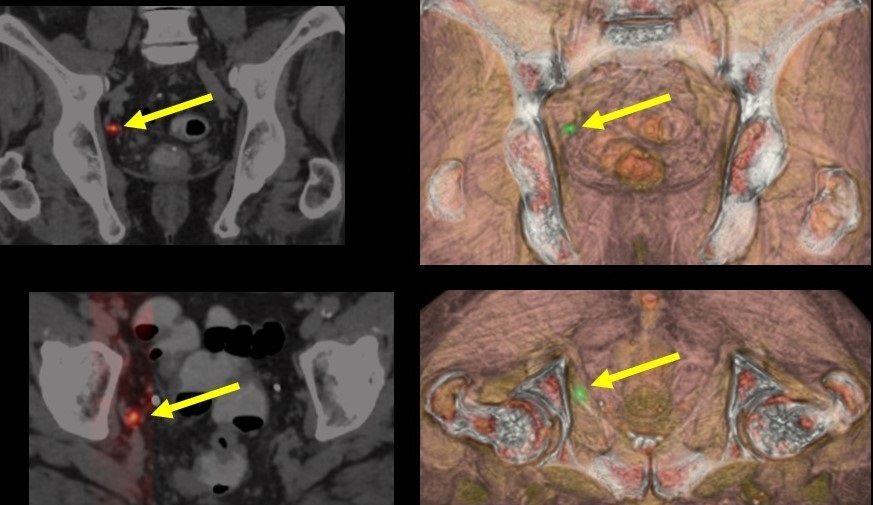

El doctor Bernardino Miñana, director del Centro de Próstata de la clínica, ha destacado que esta terapia se destina a pacientes con tumores de bajo o mediano riesgo, en quienes el cáncer es visible mediante resonancia magnética y que desean evitar tratamientos radicales, como la cirugía o la radioterapia tradicional. Para asegurar los resultados, es clave una rigurosa selección de los candidatos, que incluye la realización de resonancias magnéticas y biopsias transperineales con sistemas de fusión, técnicas que permiten una caracterización detallada del tumor.

La electroporación irreversible es una técnica no térmica que utiliza pulsos eléctricos de alto voltaje para destruir células cancerosas sin afectar de forma significativa el tejido circundante. Este tipo de ablación ha sido adoptado por más del 10 % de los pacientes en el Cáncer Center de la Clínica Universidad de Navarra, y es cada vez más reconocido por su eficacia y por los beneficios en términos de calidad de vida. En paralelo, el centro continúa investigando tratamientos combinados para casos de cáncer de próstata de alto riesgo, como la combinación de cirugía y radioterapia, en un intento por ofrecer alternativas que también conserven la continencia y el bienestar del paciente.